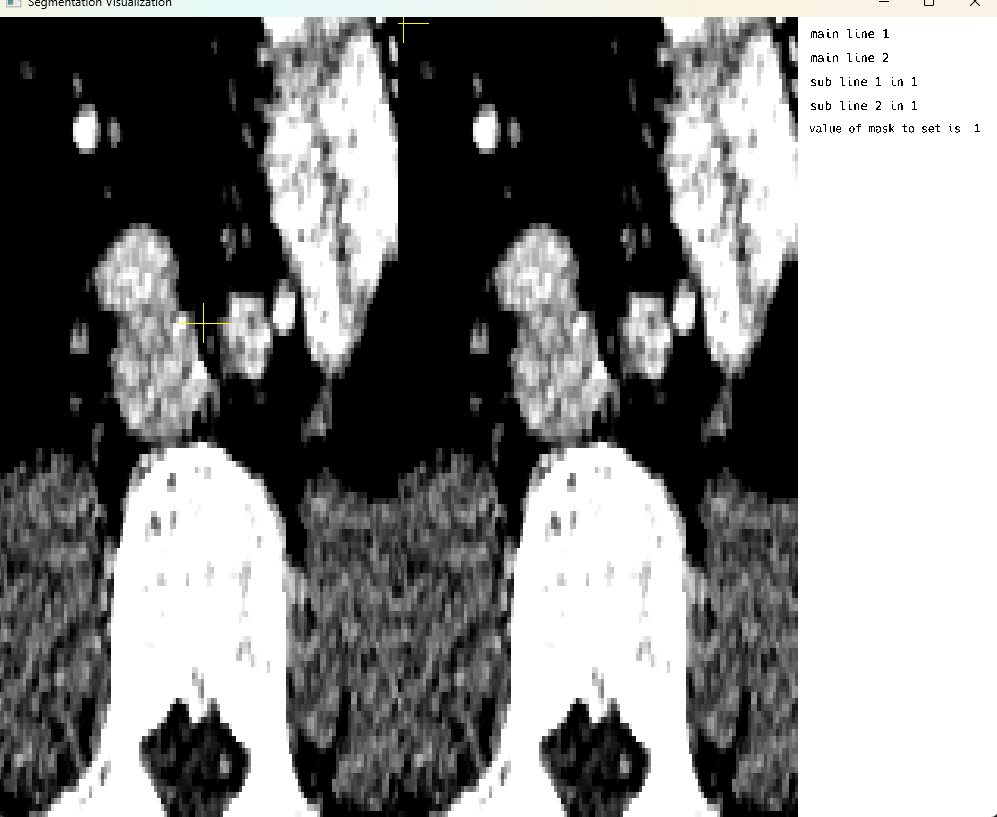

Multi Image Mode: Crosshair rendering

This cell demonstrates multi-image display mode with crosshair rendering functionality. The crosshair feature allows users to visualize corresponding locations across multiple medical images simultaneously, which is particularly useful for comparing different imaging modalities or different time points of the same patient. Note that on-screen voxel modification is currently only supported in single image display mode.

using MedEye3d

medEyeStruct = MedEye3d.SegmentationDisplay.displayImage(h5ImagesArg) #multi image displaysKey Features Demonstrated